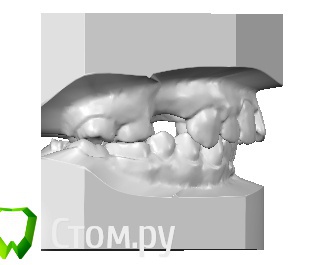

2,5 года прохожу ортодонтическое лечение на брекетах  системы Виктори ( металлических)., в последствии буду протезироваться на имплантах

У меня есть  сомнения насчет результата лечения,в частности я недовольная овалом лица и нижней челюстью.

Прилагаю все имеющиеся снимки ( до и сейчас) и фото данный момент.

2-смущает окклюзионная плоскость на нижней челюсти.

4-Так же стоит обратить внимание на изменения в суставе, возможно стоит дообследоваться, опять же, по ОПТГ об этом не судят, но изменения есть, скорее всего это связано с отсутствием моляров. Проблемы с ассиметричным положением нижней челюсти решаться, с исправлением окклюзионнй плоскости, и восстановлением межальвеолярной высоты.